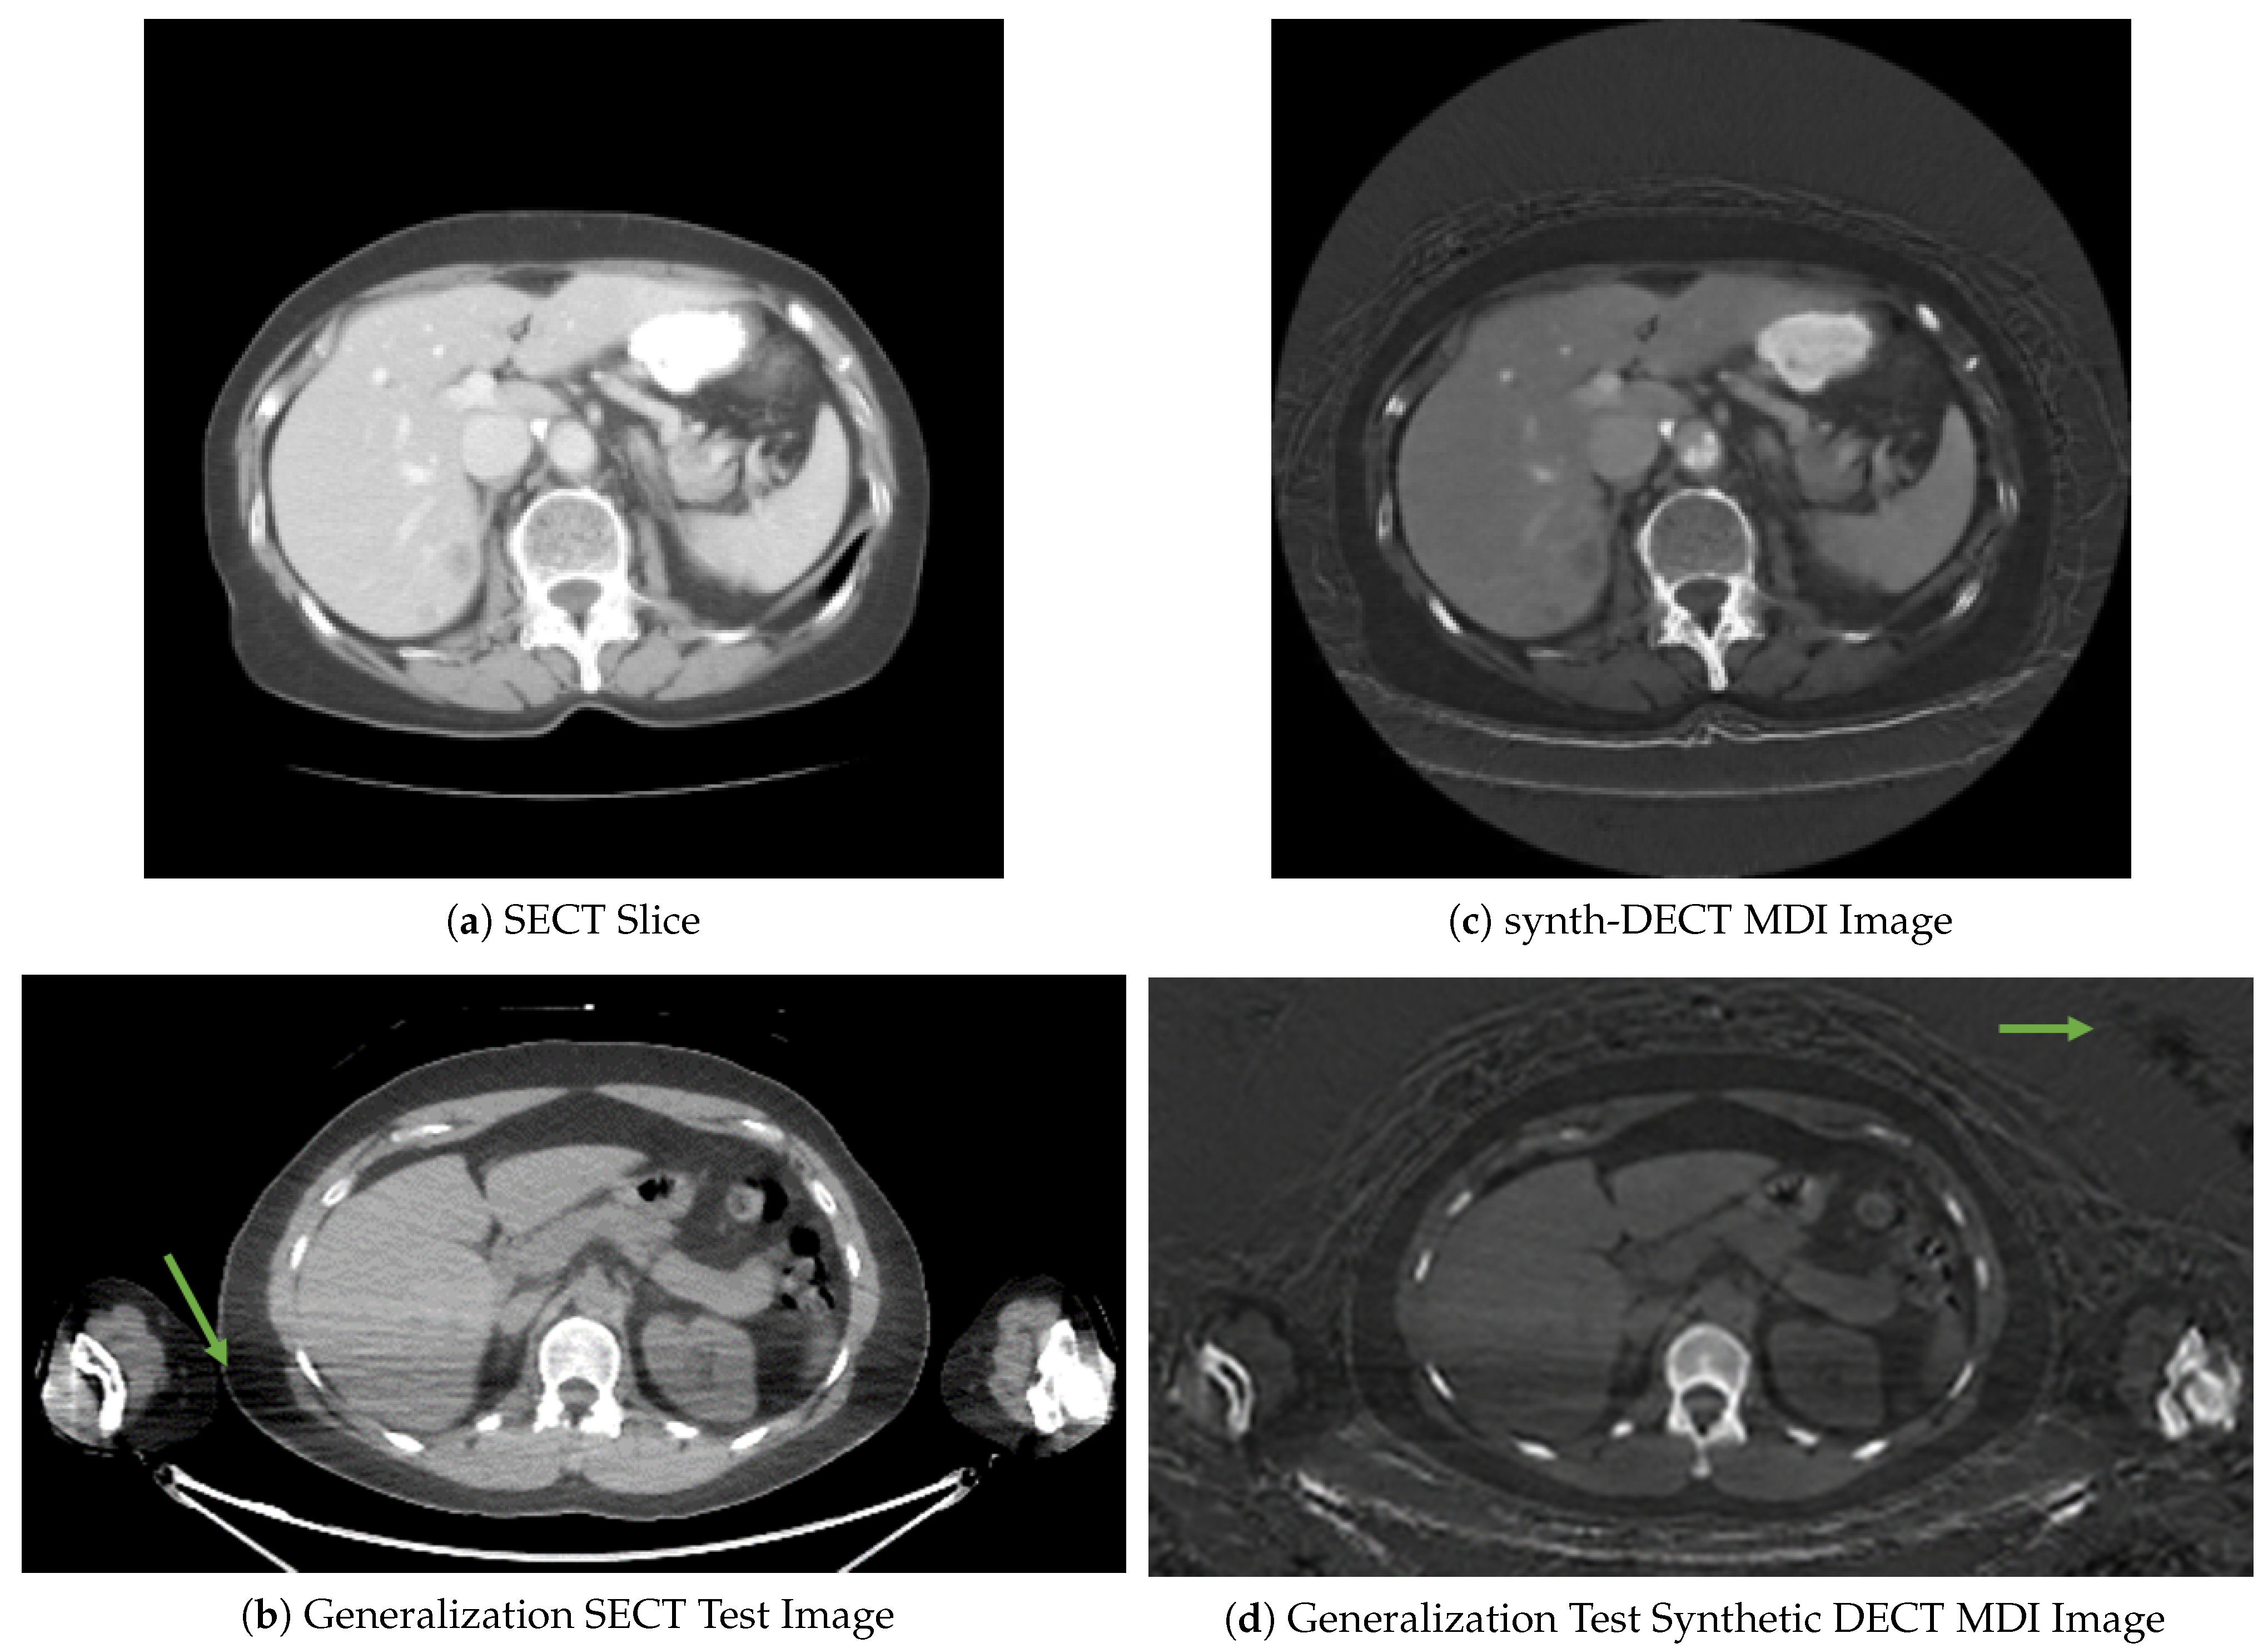

Figure 2. Cross sectional axial slices comparing the image-to-image translation for scans in CT-ORG. (a) A single axial slice from a patient single energy CT (SECT) scan. (b) Representative slice from one of the nine PET/CT scans used as the generalization test set: The streaks pointed to by the arrow are photon starvation artifacts that result from excess attenuation caused by the arms being at the side during the scan. (c) The synthetic dual energy CT material density iodine (synth-DECT MDI) image for the slice shown in (a). (d) The synth-DECT MDI image of the slice is shown in (b). The arrow in the synthetic slice shown in (d) points to a region in the air surrounding the patient that was distorted.

The translation outcomes for two sample scans from the training and generalization test sets are shown in Figure 2. Subjectively, the anatomical structures are translated correctly. However, in the original SECT slices shown in Figure 2a,b, the bedding surrounding the patient seen in Figure 2c,d was not present. Because our objective was liver segmentation, the hallucinated bedding was excluded from subsequent tasks by first creating a binary mask of the body and then extracting only the pixels containing body information using the mask. The slices in Figure 2b,d are from a patient’s PET/CT scan in the generalization test set. The streaks indicated by the arrow in Figure 2b are due to the arms being down at the patients side and the use of a low dose CT scan. The synthetic counterpart shown in Figure 2d appears similar except for the distortions in the air surrounding the patient. Although distortions were evident in the synthetic slices, they reside outside of the body habitus; thus, they were not found to interfere with downstream tasks. With acceptable translation accuracy, we now evaluate our hypothesis that systems trained using the synth-DECT MDI scan types enable generalization with limited data.